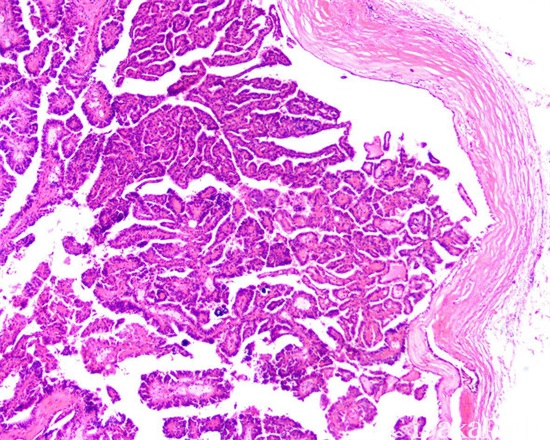

(3)X线检查

坏死型:第一种为肾盏模糊,后在肾盏处形成盲管,盲管逐渐结合,造影时呈“弓形”或“环形”图像;坏死肾乳头入盆后充填破坏,乳头呈棒状空腔,坏死的乳头充填缺损,近端扩大。坏死乳头周围可见钙,盐沉后,在扁平膜上出现环状钙化。

髓坏死型:当坏死组织在锥体深处,与肾盏不相通时,造影未发生变化,形成瘘管,肾盏连接在肾盏上。